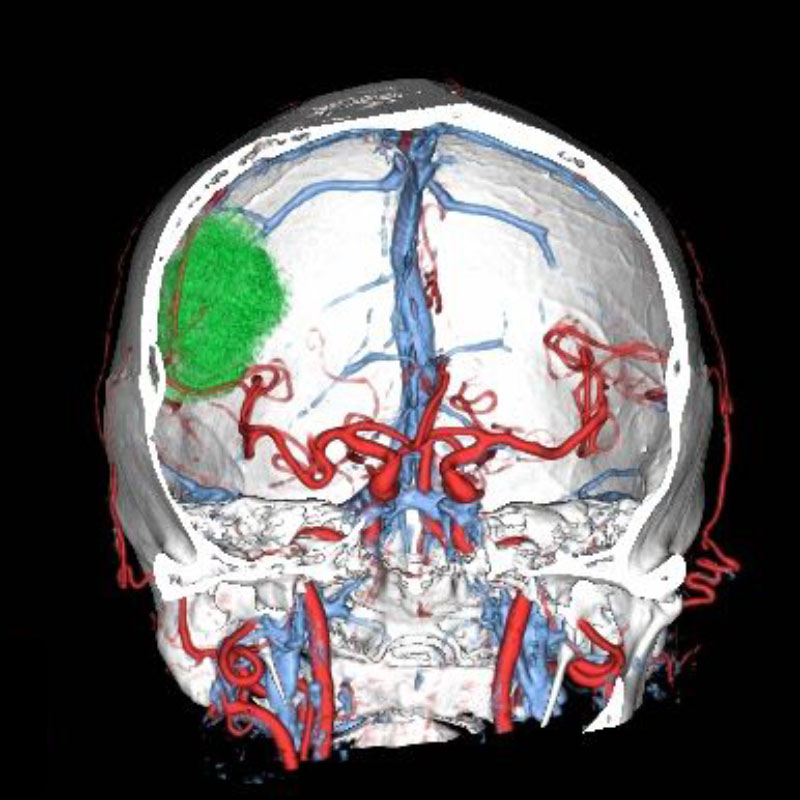

699

'25年11月

50代

左前頭葉腫瘍

頭蓋内腫瘍摘出術

No.’25_101 手術前1

No.’25_101 手術前2

No.’25_101 摘出 前

No.’25_101  摘出 中

No.’25_101 摘出 後